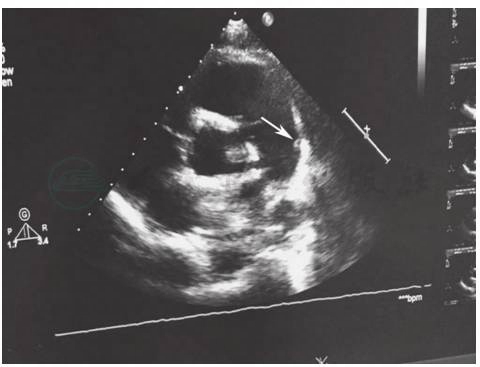

超声心动图(2015年3月24日):根据影像学检查提供的信息,再次行超声心动检查,发现动脉导管开口对侧肺动脉壁有黄豆大小赘生物,随血流漂动(图10)。

图10 超声心动图

引自:主编:.呼吸系统疑难病例诊疗辨析.第1版.ISBN:978-7-117-26415-0